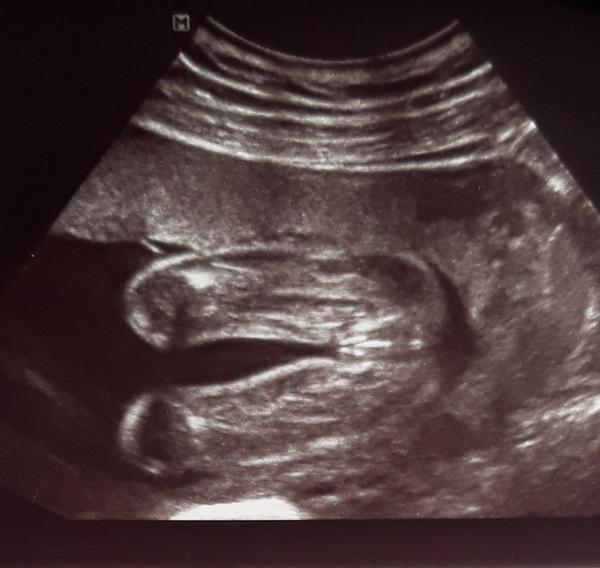

Poznáte z ultrazvuku pohlaví?

Ahoj🙂co myslíte, je to pinďa nebo pipka?😄

No právě mně jednou doktor řekl jasnýho chlapečka a podruhý, že to vidí spíš na holčičku, ale jako pipka se mi to nezdá..😄 a ještě před ultrazvukem jsem si sama myslela chlapečka, takže mě to zaskočilo😃